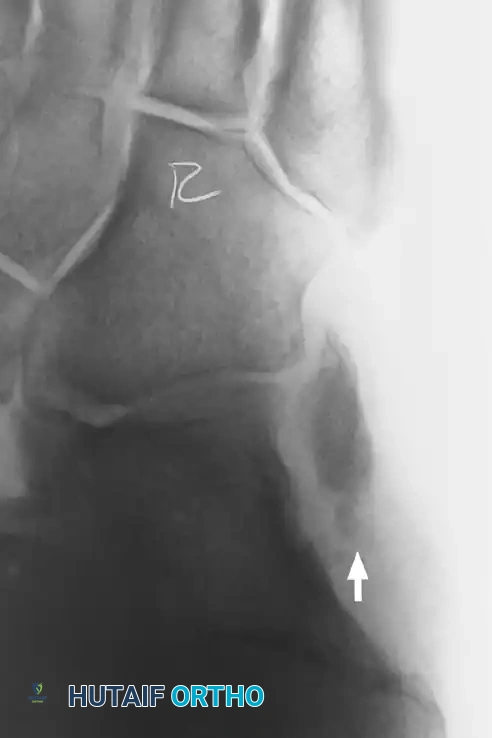

Figure 82-47: (A) A 61-year-old man with a rupture of the peroneus longus tendon and a varus right foot. (B) Note the hypertrophic os peroneum and its proximal migration following the rupture.

- Plain Radiographs: Essential for identifying bone avulsions (e.g., "fleck sign" of the superior peroneal retinaculum) or the proximal migration/fracture of an os peroneum.

Figure 82-48: (A and B) Radiographs demonstrating a tear of the peroneus longus with proximal retraction of the sesamoid bone (os peroneum). (C) T2-weighted MRI showing a type I tear of both the peroneus longus and peroneus brevis tendons.